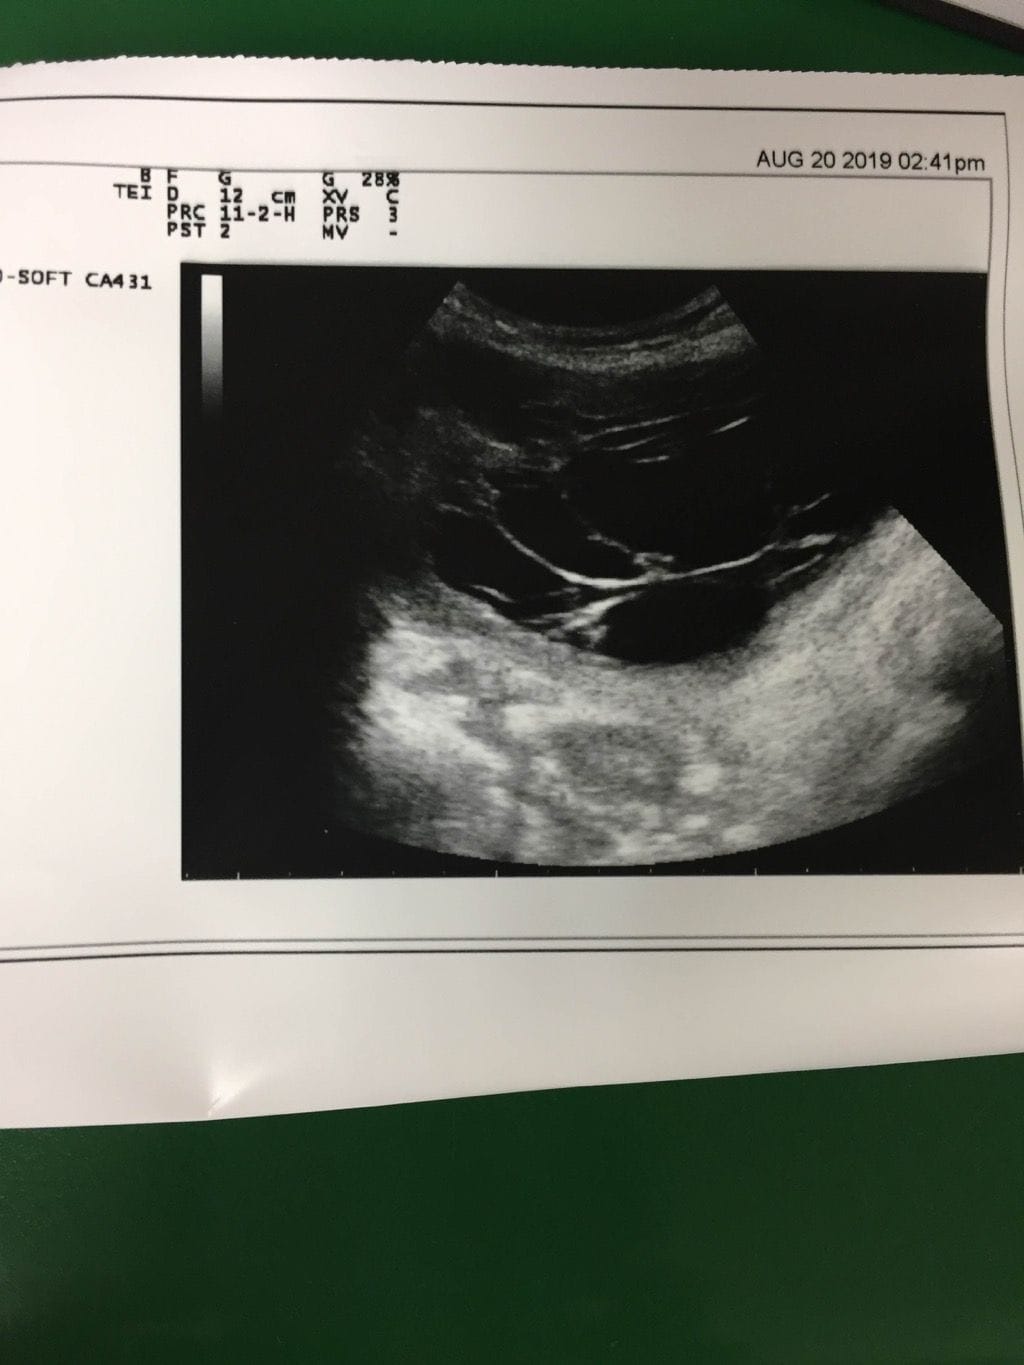

病人的 Chest X-ray 並沒有看到肺結核的特徵,留了兩套痰做 Acid-fast stain 也是陰性,第三套因為病人沒有痰在換月時遲遲沒有留出。讓人起疑的是腹水的超音波。

超音波下可以看到具有 loculated ascites 的特徵,請教學長後必須懷疑感染 peritonitis 或 Peritoneal carcinomatosis ,如果已經多次做過 Adominal tapping 放過多次腹水也有可能呈現這樣,但是病人是第一次放腹水。